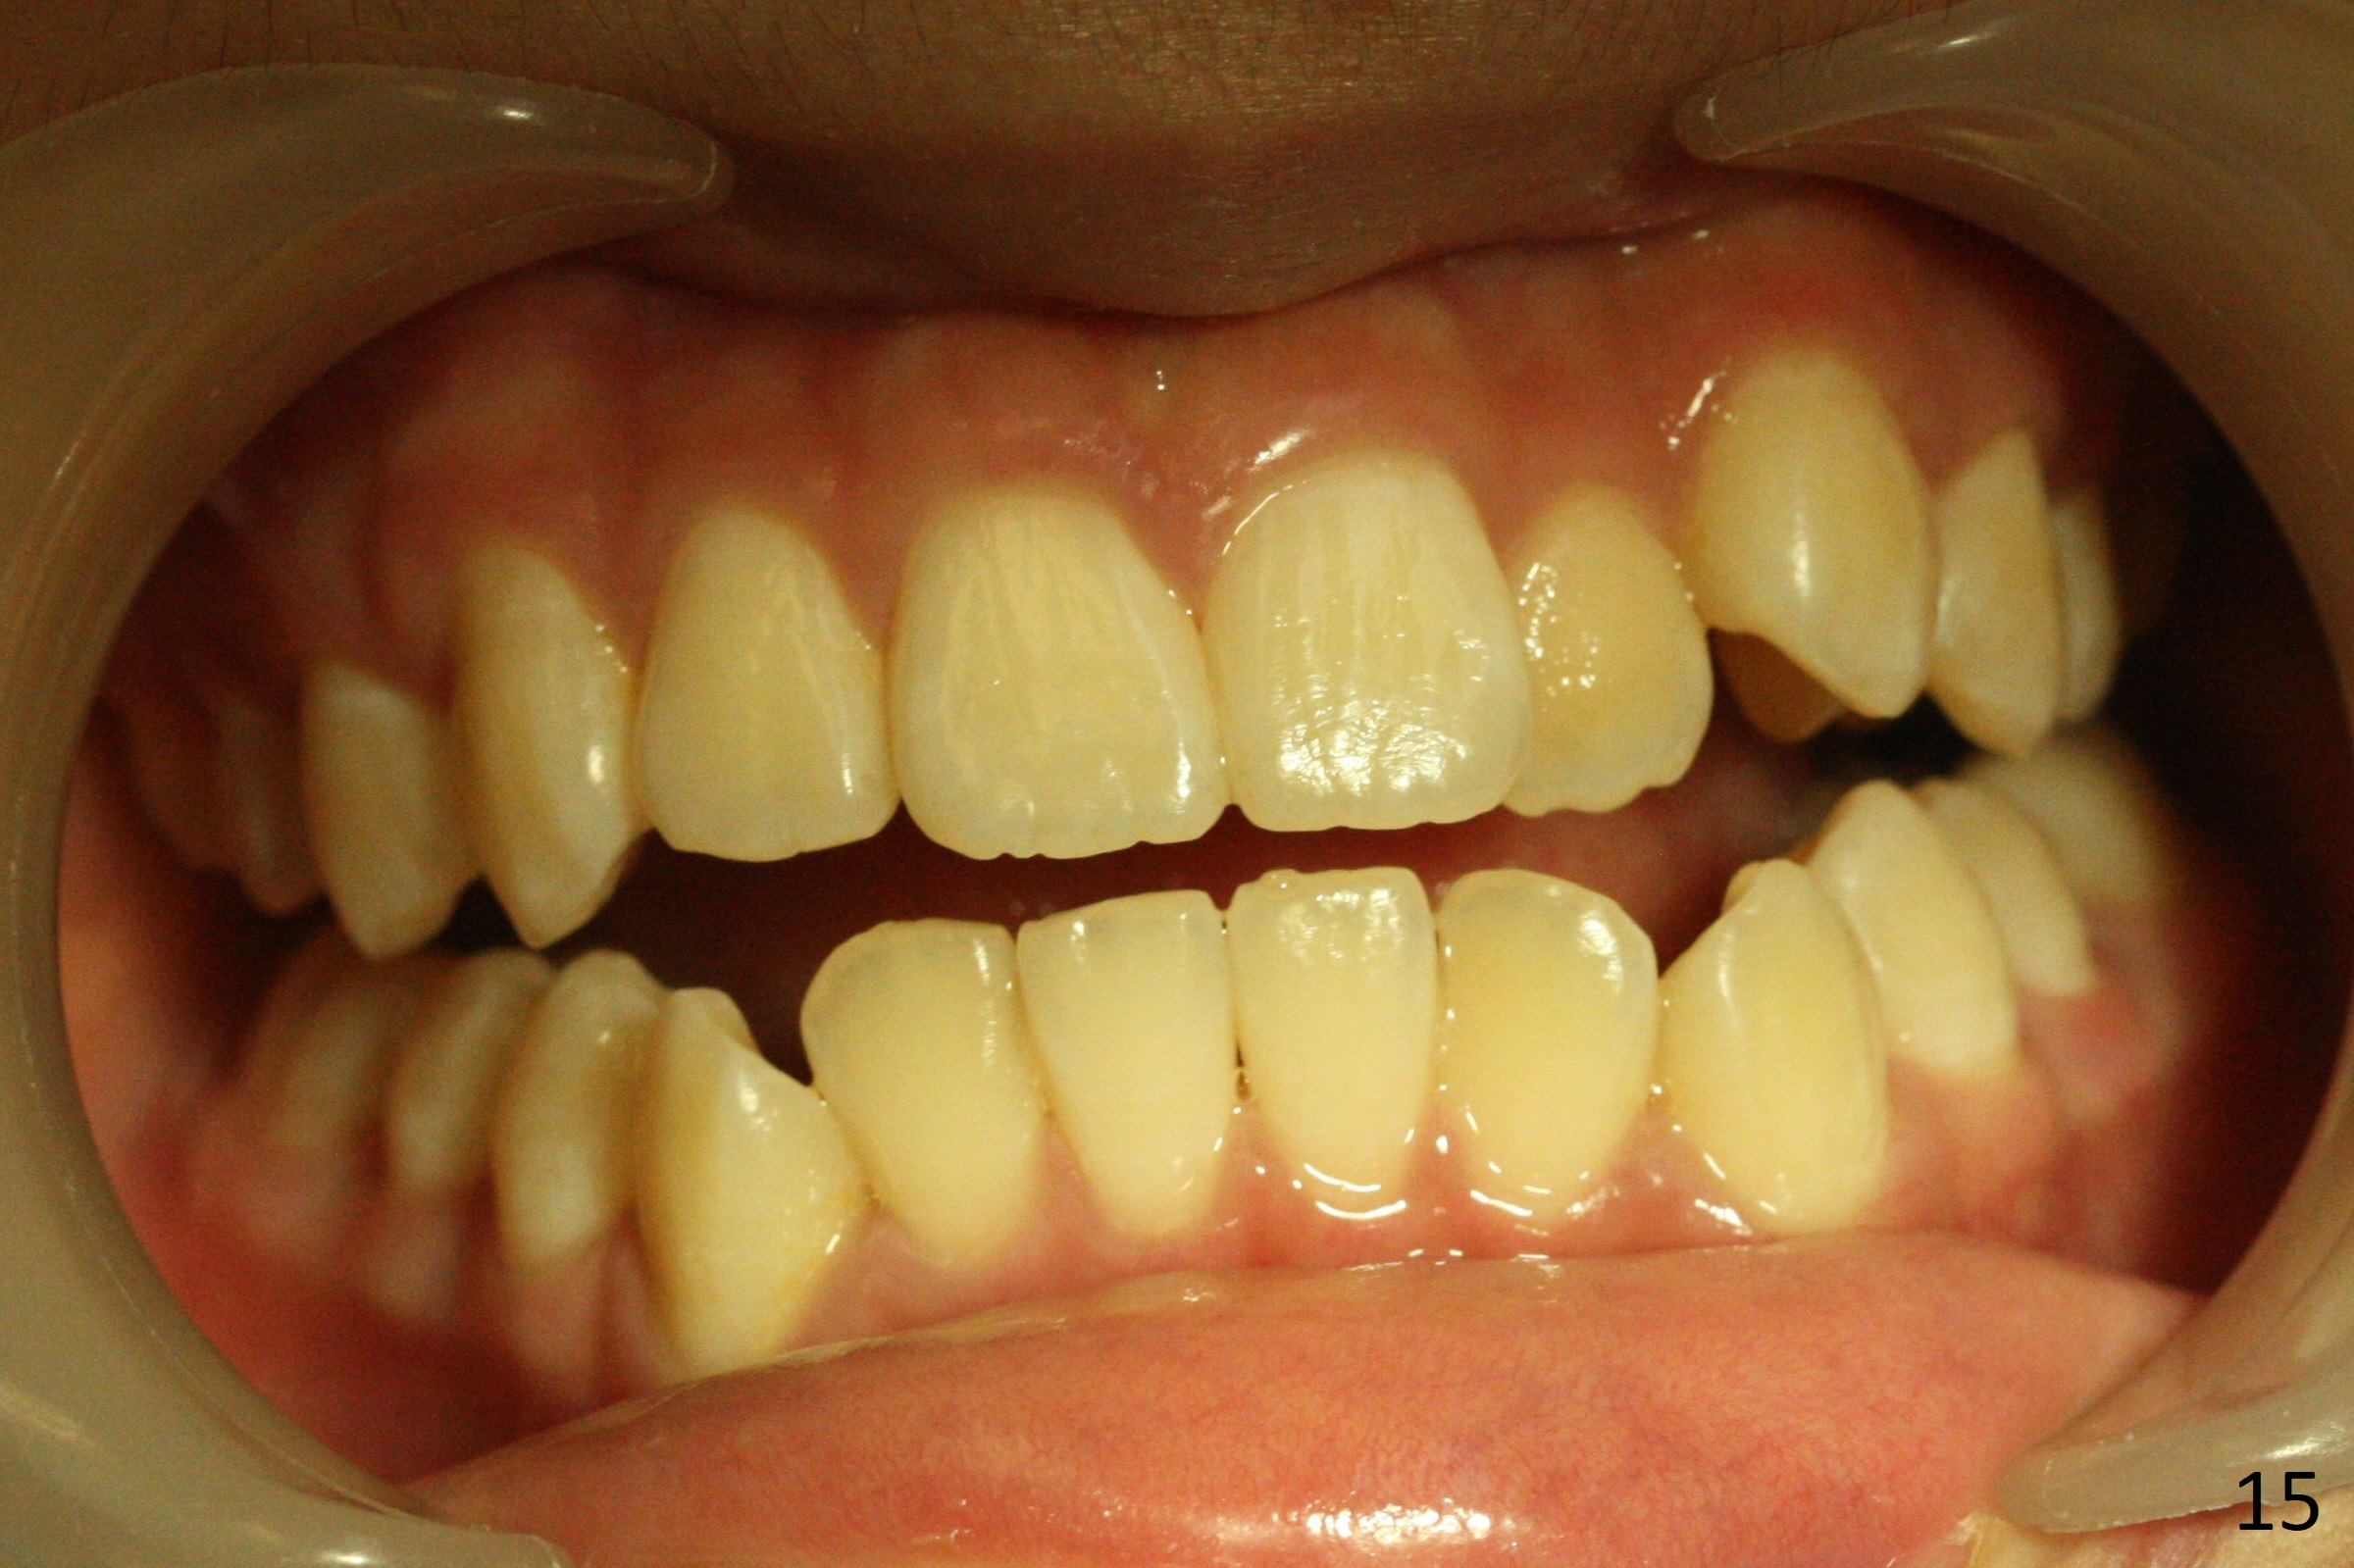

Shallow Overbite

A 12-year-old man has mild lip protrusion (Fig.1,6,7). Orthodontics will be conducted without extraction. Unlike his elder brother, the overbite is shallow. With anterior bracket differential (4-4-5 mm) and mild bimaxillary protrusion, open bite will be created? Or 4-4-4.5mm scheme should be adopted to avoid open bite?